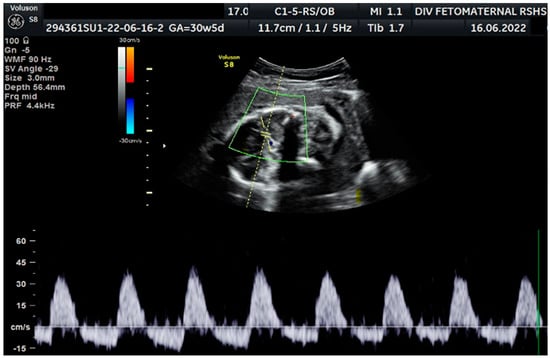

Ultrasound examination showed a cephalic lie fetus with biometry (biparietal diameter (BPD), head circumference (HC), abdominal circumference (AC), and femur length (FL)) equal to 26–27 weeks of gestation; the gestational age based on the last menstrual period was 30 weeks. The Transcerebellar diameter was equal to 29–30 weeks of gestation, and the amniotic fluid volume suggested oligohydramnios with an amniotic fluid index (AFI) equal to 1.04 cm, with an estimated fetal weight (EFW) of 956 g (<10th percentile for gestational age) (Figure 1). The structure of both kidneys and urinary vesica was within a normal range, and fetal structural abnormalities were difficult to assess. The placenta was located anteriorly.

Figure 1. Amniotic fluid index (AFI 1.04 cm): oligohydramnios.